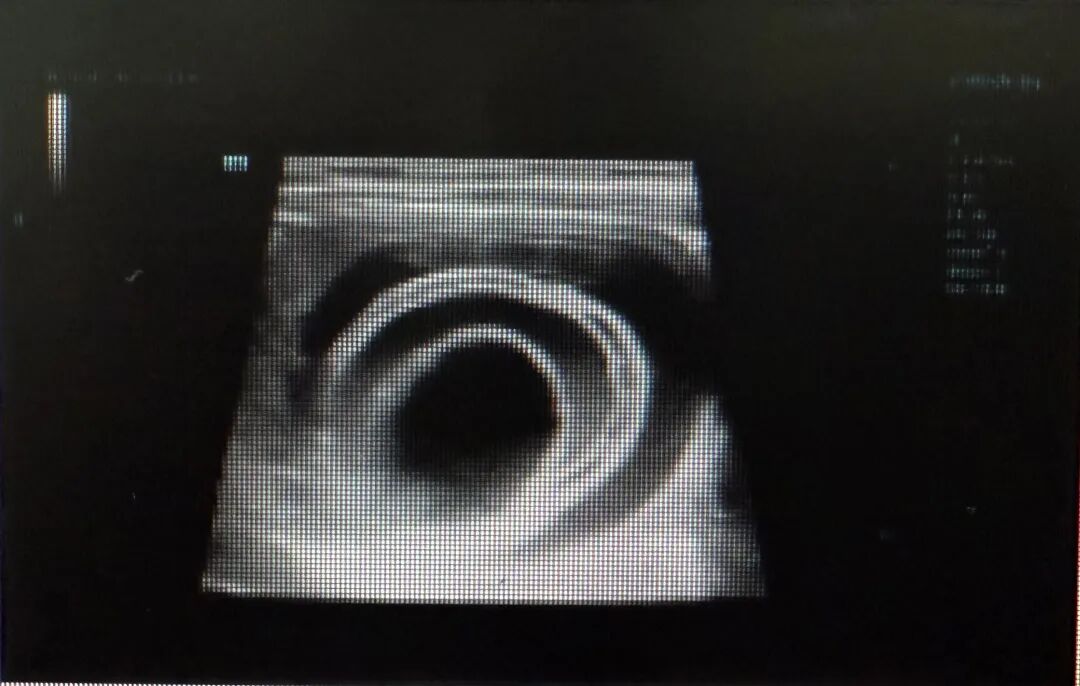

卵巢怎么会突然 “打结”?本质是 “供血线” 被拧断了

妇科主任说,其实卵巢蒂扭转很好理解,卵巢(通常还带着囊肿或肿瘤)像拧毛巾一样转了好几圈,把给它供血的血管死死压住。血管一堵,卵巢就成了 “断粮” 的器官,缺血、缺氧跟着来,时间一长,直接坏死。

1.定期做妇科 B 超:卵巢囊肿是扭转的 “头号帮凶”,体检时发现 5cm 以上的囊肿,别拖延,听医生建议处理(比如观察、用药或手术),别等它长成 “大炸弹”;